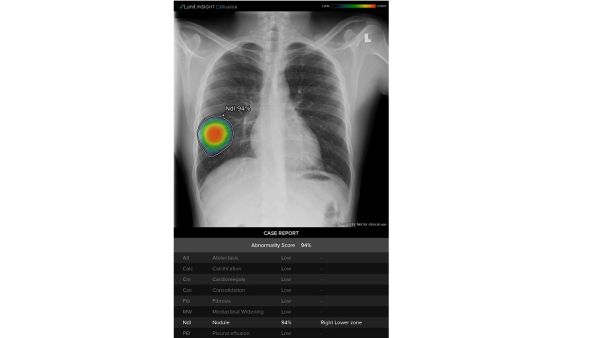

وتستفيد "منظومة العناية الصدرية" من قوّة الذكاء الاصطناعي للمساعدة في الحد من هذه الضغوطات من خلال تحليل تلقائي للصور يرصد ثماني نتائج غير طبيعية للتصوير الشعاعي، بما في ذلك الاشتباه بالإصابة بمرض السل والالتهاب الرئوي، وهي أعراض يمكن أن تشير أيضاً إلى الإصابة بمرض "كوفيد-19". وعند قراءة التقرير في أنظمة أرشفة الصور وأنظمة الاتصالات (PACS)، يمكن للمتخصصين في التصوير الشعاعي التعرف بسرعة على حدة الأعراض غير الطبيعية الثمانية المحتملة، وإجراء عملية تركيب الصور، ووصف موقع الإصابة كتابياً بما يثمر في تسريع وتيرة التشخيص والعلاج.

وتوفر "منظومة العناية الصدرية" الدعم الضروري للمساعدة في التعرف بسرعة على الحالات عالية الخطورة بالإضافة إلى مراقبة المرضى الذين يظهرون تطور وتراجع أعراض الجهاز التنفسي الخفيفة. مع معدل دقة يبلغ 97%-99% (المنطقة تحت المنحنى AUC)، وتم تخصيص الخوارزميات الفعالة التي تدعم تقنيات الذكاء الاصطناعي لاكتشاف نتائج الفحوص الإشعاعية في غضون ثوان معدود ة. وفي إحدى الدراسات، أظهرت النتائج انخفاضاً بنسبة 34٪ في وقت القراءة لكل حالة مرضية.

وإضافة إلى الكشف عن الالتهاب الرئوي، تدعم "منظومة العناية الصدرية" أمراضاً مثل السل؛ وانخماص الرئة؛ والتكلس؛ وتضخم القلب؛ والتليف؛ واتساع المنصف؛ والعقيدات الرئوية؛ وكشف الانصباب الجنبي.